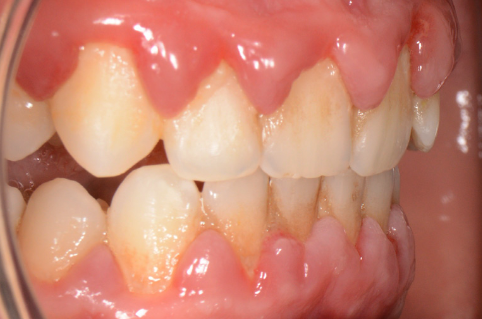

Cel mai vulnerabil punct al parodonțiului este șanțul gingival, ce se află la baza dintelui, între acesta și marginea gingivală liberă. Placa bacteriană și tartrul neîndepărtate corect printr-o igienă riguroasă se acumulează la acest nivel și reprezintă cauza declanșatoare a unei inflamații parodontale. Trebuie de asemenea înțeles de ce placa bacteriană are un efect distructiv asupra țesuturilor dentare: o parte din bacteriile prezente în cavitatea orală ce au ca principal suport nutritiv resturile alimentare îndepărtate prin periaj secretă o serie de toxine ce atacă suportul biologic al gazdei. (Fig. 5.1.1 și 5.1.2)

În cazul apariției oricărui tip de sângerare gingivală, pacientul este sfătuit să se adre- seze medicului parodontolog. Gingivita, fiind prima etapă inflamatorie din parcursul bolii parodontale, este complet reversibilă, atât timp cât este identificată precoce. (Fig. 5.1.3, 5.1.4)